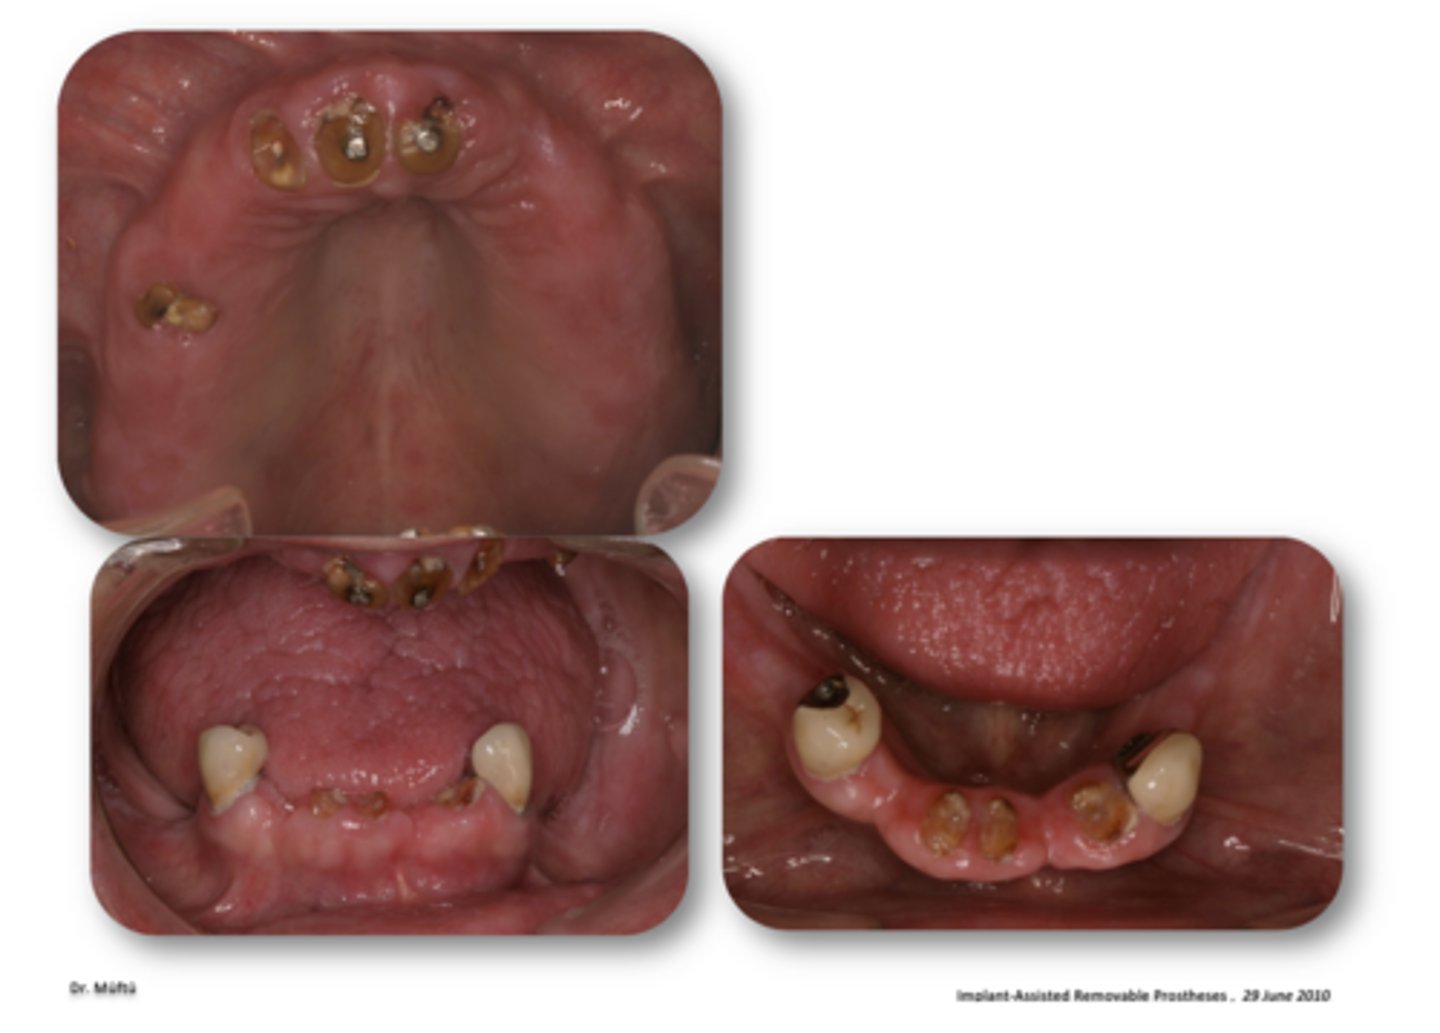

Maxillary implant ODs

The following are patients who benefit from what?

- Younger segment of older pts (50-60)

- No experience with maxillary removable prosthesis

- Hopeless residual maxillary dentition

- Fearful of becoming edentulous

- High esthetic demands

- Natural teeth or fixed pros in mandible

- Desire fixed reconstruction